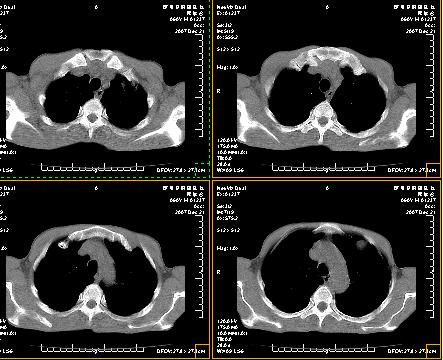

标题: CT12370:男.60岁.咳嗽发热胸痛. [打印本页]

标题: CT12370:男.60岁.咳嗽发热胸痛.

两肺及胸膜多发性转移瘤。纵隔淋巴结转移.

双侧胸壁见多发结节软组织密度灶,两肺内见广泛结节状、面团样影,两肺及胸膜多发性转移瘤。支持

考虑肝癌双肺转移!腹部强化确诊吧。

根据:病变确实是多发,但大部分边缘不光滑,欠规整,密度不均匀。也就是说“大部分病灶不是典型转移瘤的表现”。转移瘤可以不典型,但如此大部分不典型,却是很少见的。结合发烧病史,考虑肺多发小脓肿或其他炎性病变,如霉菌等感染!建议痰培养,抗炎治疗后复查!